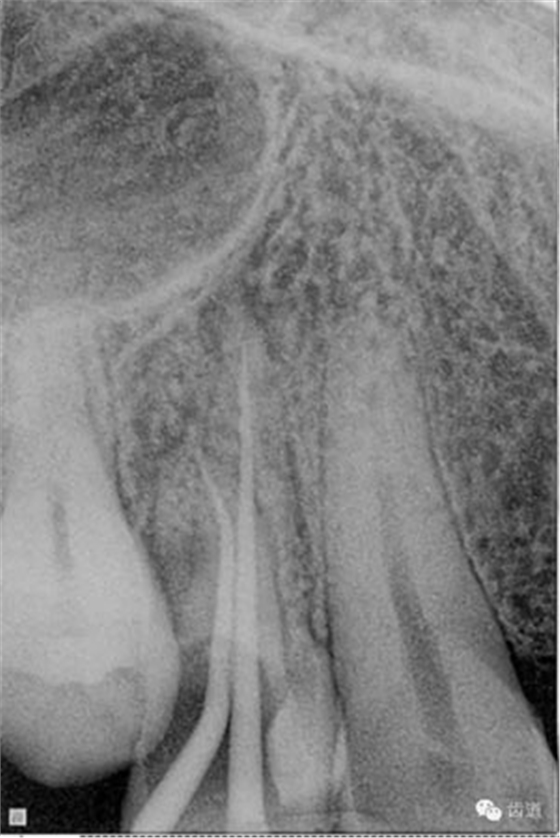

數(shù)碼x攝影顯示:近中頰根及腭根根管充填恰填,遠(yuǎn)中根管有遺漏。

顯微鏡下反復(fù)探查根管,未探及遺漏根管口,放置棉球,zoe暫封。轉(zhuǎn)診上級(jí)醫(yī)生處理。

檢查顯示:近頰及腭根充填恰填,遠(yuǎn)頰根管內(nèi)有少許充填物影像。根尖明顯低密度影像。